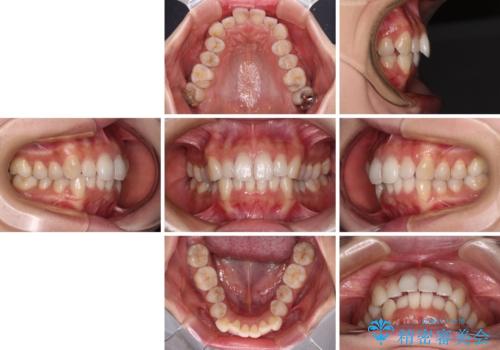

- デコボコと飛び出している前歯を気にして来院された患者様です。

歯列としてはインビザラインでもワイヤー矯正でも対応できるものでしたが、奥歯の咬み合わせを見た時に上顎がやや前方にあり、インビザライン単独では時間のかかってしまう可能性があるため、補助装置を治療当初に使用することで、インビザラインによる治療をスムーズに行えるように計画しました。